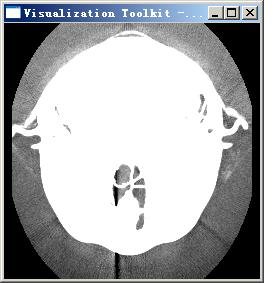

將vtkdata目錄下的fullhead15.png文件拷貝至該項目的debug目錄下,并在command窗口中將工作目錄指定為該項目的debug目錄,輸入:myProject.exe fullhead15.png, 將得到如下結果